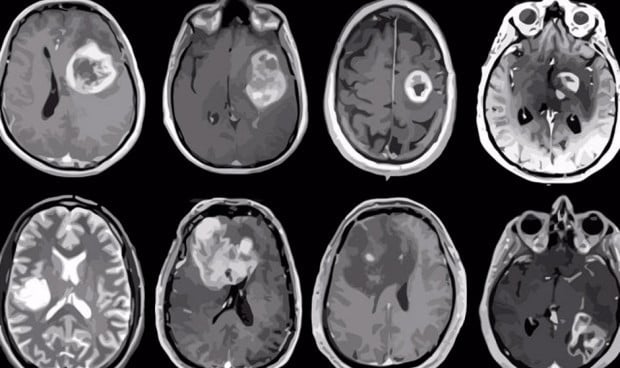

El glioblastoma es uno de los tumores sólidos tratado con el nuevo método.

La terapia con células CAR-T ha demostrado grandes resultados frente a distintos tipos de cáncer, pero la pérdida del antígeno sigue siendo un obstáculo a superar por los especialistas a la hora de abordar tumores sólidos. Un estudio publicado en la revista Cell demuestra en ratones que gracias a una vacuna in vivo, el sistema inmunológico mantiene el potencial de la CAR-T, aumentando la posibilidad de erradicar estos tumores, en concreto de glioblastoma y melanoma.

Para determinar si las células T afectaban al resultado del tratamiento CAR-T, unos ratones portadores de tumores, en concreto de glioblastoma y melanoma, recibieron la vacuna y otros no. Después de analizar los linfocitos infiltrantes de tumores (TIL) en ratones y añadirles el refuerzo de la vacuna al tratamiento con terapia CAR-T, a partir del séptimo día los investigadores observaron un aumento notable de TIL y una tendencia hacía el aumento similar en la infiltración de células T huésped.